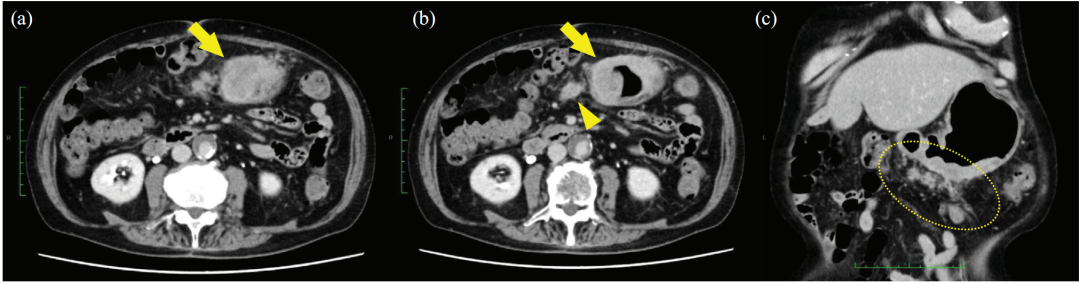

影像学评价: 治疗第 56 天,CT 显示原发病灶显著缩小,腹膜播散灶消失。治疗 5 个月后,第二次 CT 评估未发现原发灶增加或转移迹象。